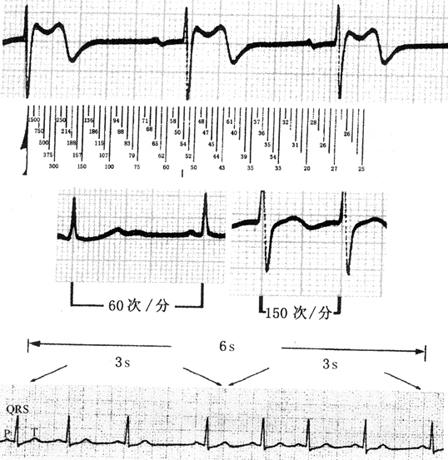

心电图走纸速度常采用25mm/s,使1mm横向间距=0.04s。定标10mm,1mm振幅相当于0.1mV。根据波幅大小,应调整电压参数。

心电图的测量如图19所示。不同走纸速度描记的心电图如图20所示。

图19 心电图的测量

图20 不同走纸速度描记的心电图

·6s或3s计算法;

·R-R间距测量法;

·心率计算尺测量法;

·R-R间距小格计算法(表2)。

表2 R-R间期中小格(0.04s)数与心率的关系

心电图的测量方法如图21所示。

图21 心电图的测量方法